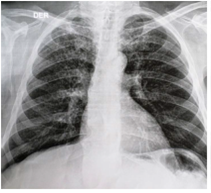

En la radiografía de tórax se apreciaron opacidades retículo-nodulares en ambos campos pulmonares (figura 2), hallazgos confirmados por TC (figura 3). La baciloscopia seriada de esputo fue negativa para bacilos ácido-alcohol resistentes (BAAR), y en la colonoscopia y la ileoscopia practicadas se encontró ileítis, una tumoración ulcerada junto a la válvula íleocecal y una lesión ulcerada en el recto distal (figura 4 A y B). Se tomaron, entonces, biopsias de recto, colon e íleon cuyo estudio histopatológico informóun proceso inflamatorio granulomatoso crónico constituido por granulomas poco estructurados en todas las muestras evaluadas. Con la coloración de Ziehl-Neelsen (ZN) se demos-traron BAAR en todas las muestras (figura 5 A y B). Debido a estos hallazgos, se inició inmediatamente el tratamiento antituberculoso, además de la administración de mesalazina (4.000 mg al día).